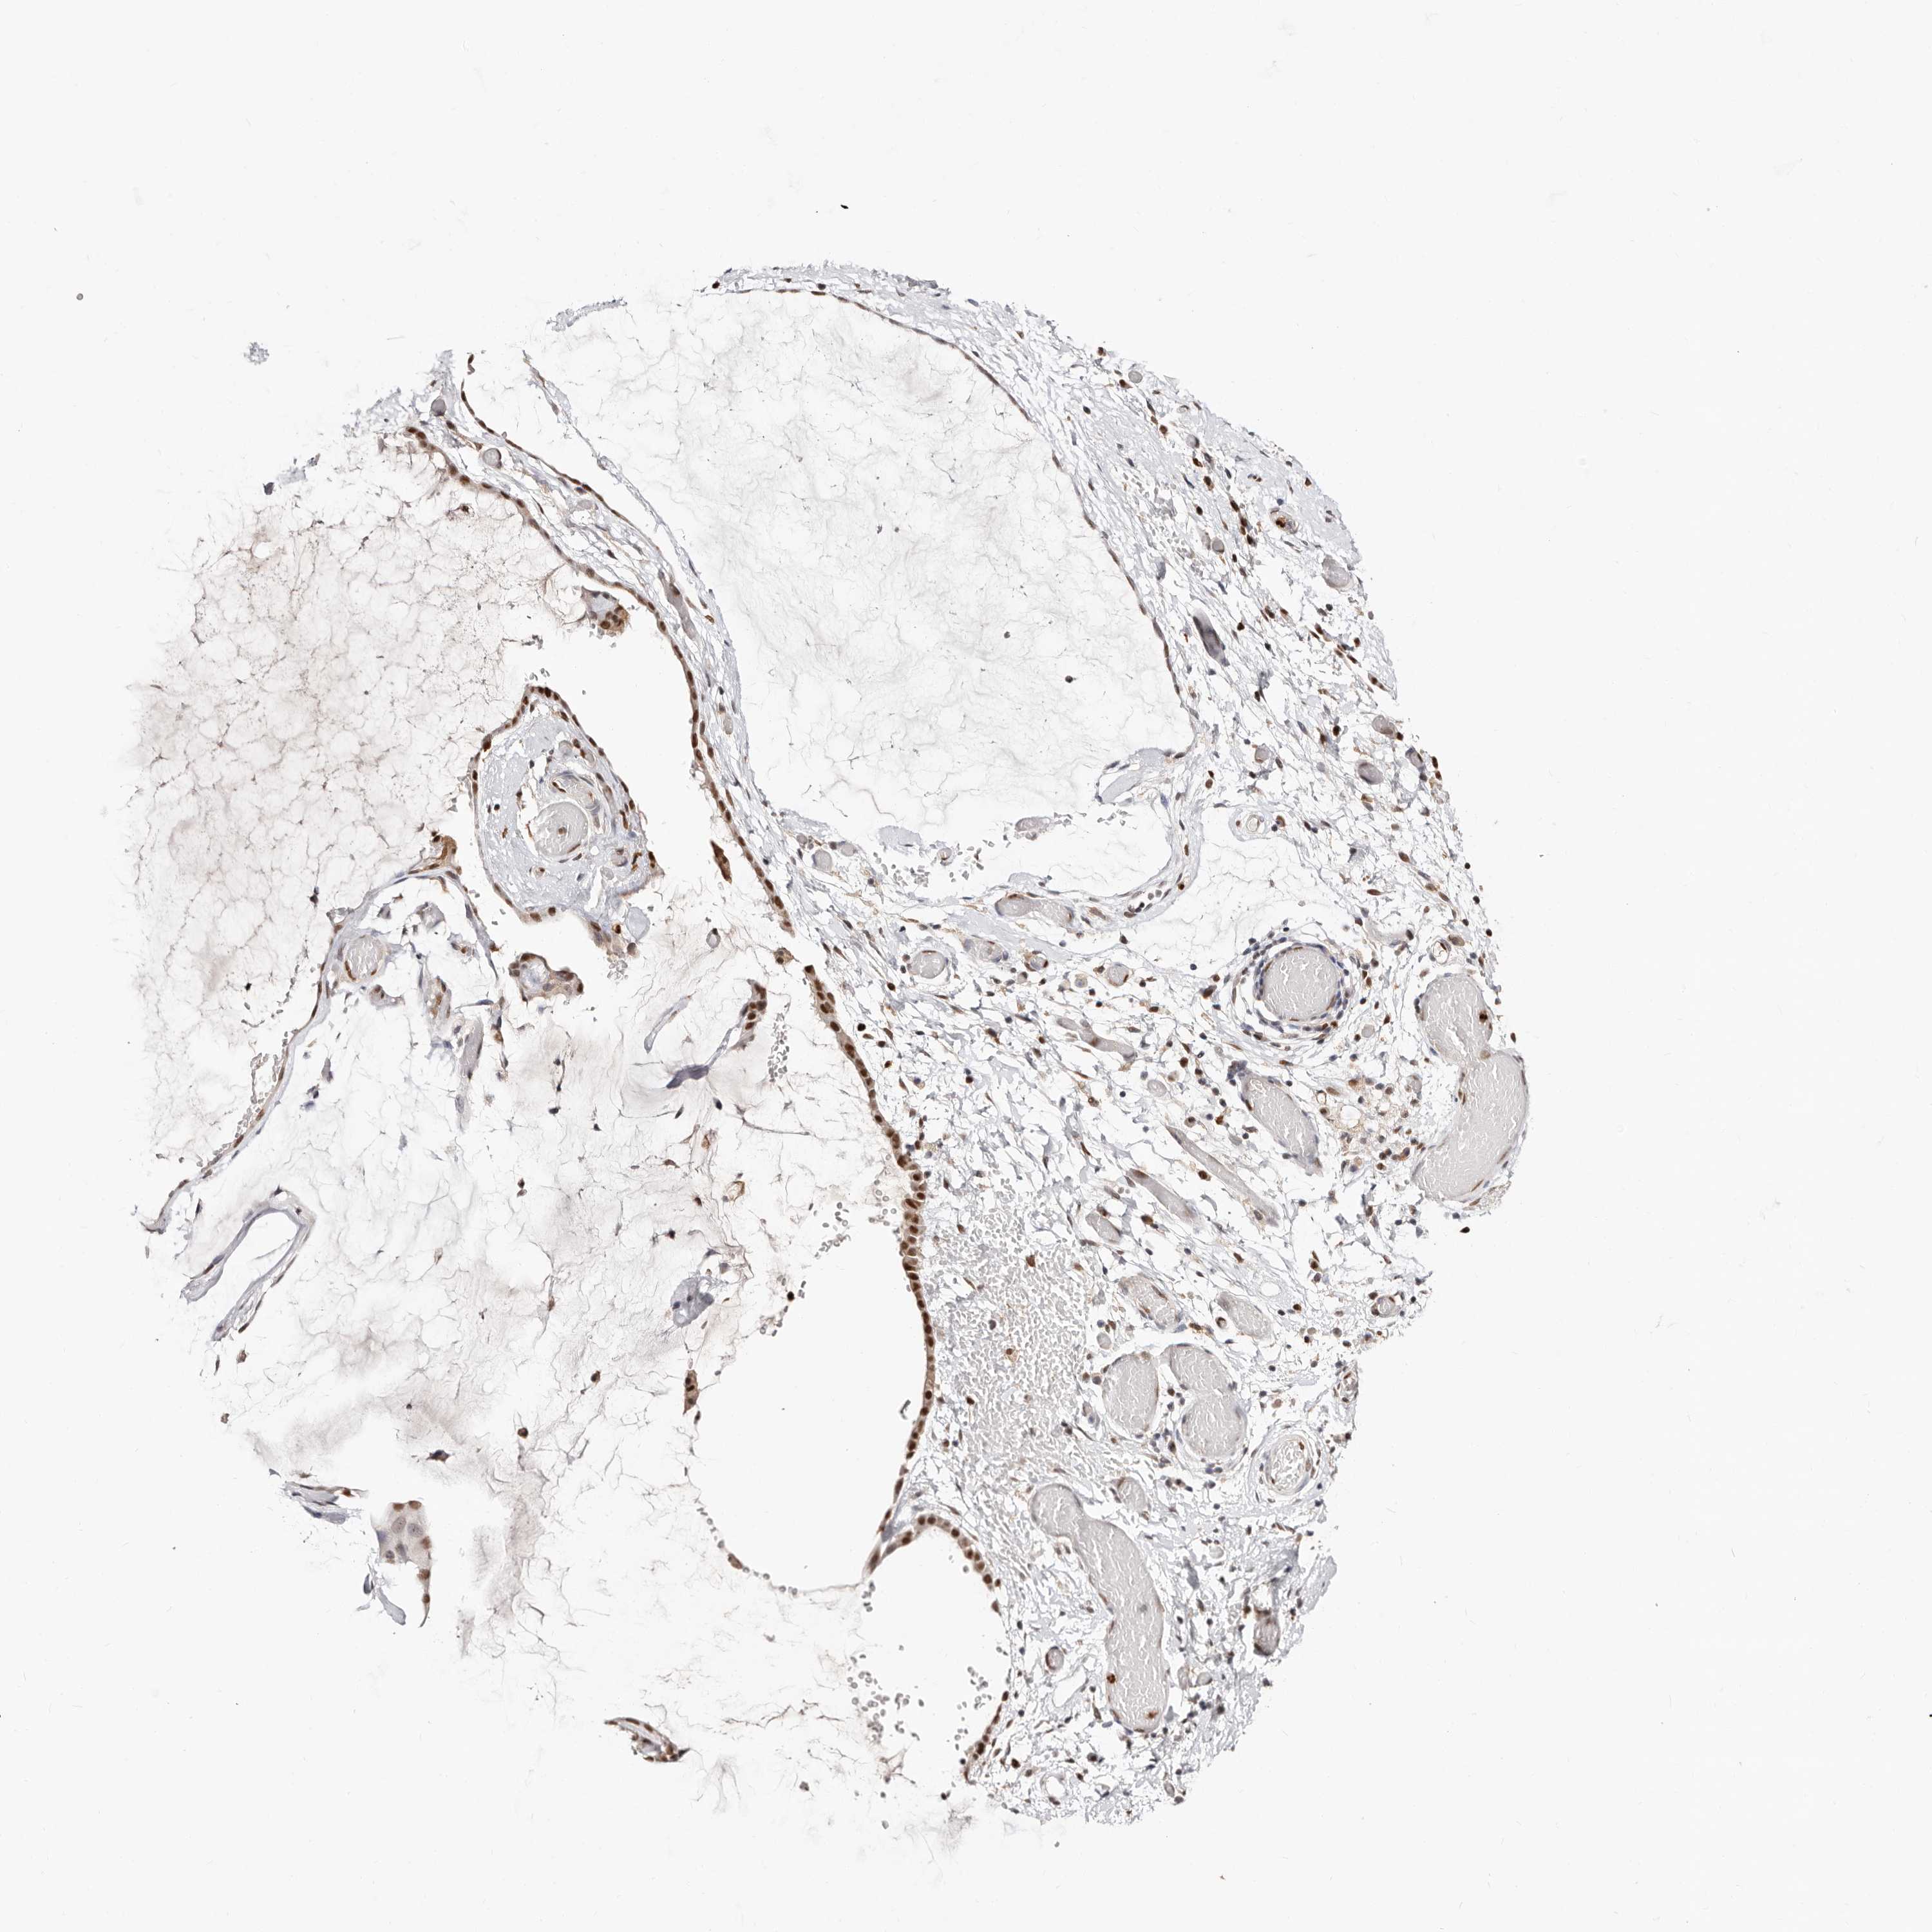

OVARIAN CANCER - Protein expressioni

A mouse-over function shows sample information and annotation data. Click on an image to view it in a full screen mode. Samples can be filtered based on level of antibody staining by selecting one or several of the following categories: high, medium, low and not detected. The assay and annotation is described here.

Note that samples used for immunohistochemistry by the Human Protein Atlas do not correspond to samples in the TCGA dataset.

Antibody stainingi

Antibody staining in the annotated cell types in the current human tissue is reported as not detected, low, medium, or high, based on conventional immunohistochemistry profiling in selected tissues. This score is based on the combination of the staining intensity and fraction of stained cells.

Each image is clickable and will lead to virtual microscopy that enables deeper exploration of all samples and also displays staining intensity scores, fraction scores and subcellular localization as well as patient and tissue information for each sample.

Antibody HPA029480

Antibody HPA029481

Carcinoma, NOS